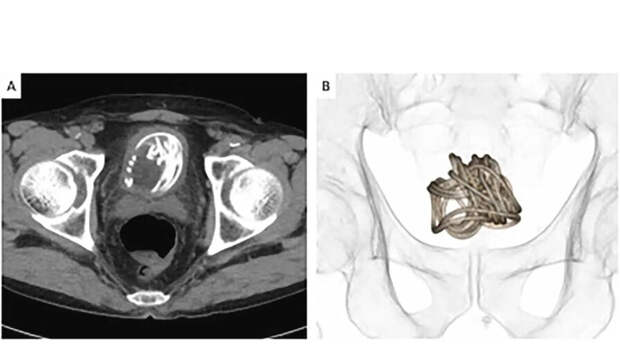

Медики хотели изъять инородное тело через уретру, однако рентген показал, что скакалка скрутилась в большой комок. В результате, чтобы вытащить веревку, хирургам пришлось разрезать мочевой пузырь.

Перед этим врачи сделали несколько подробных снимков КТ, чтобы определиться, где лучше сделать разрез. В своем отчете медики заявили, что этот инцидент продемонстрировал "неоценимую" полезность использования 3D-реконструкций для подготовки к проведению операций на мочевом пузыре.